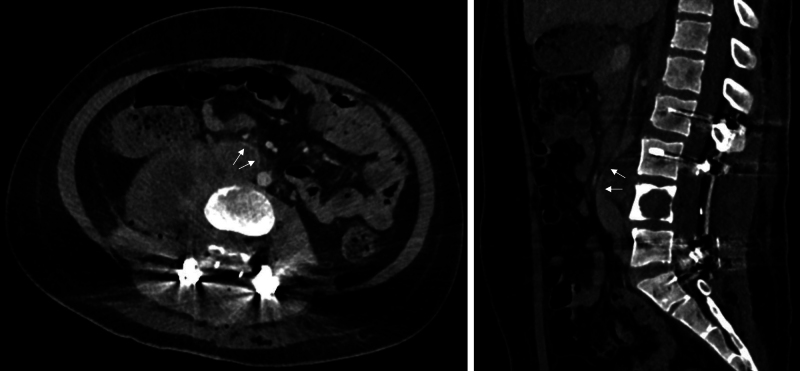

Observations: The authors present the first documented case of planned division and mobilization of the vena cava supported by venous-venous bypass in order to achieve gross-total resection of a lower lumbar malignant peripheral nerve sheathe tumor as part of a two-stage procedure.

Lessons: Inferior vena cava division and reanastomosis is a novel technique that can be used to widen surgical corridors in anterior approaches to the lumbar spine, and one that proves useful in en bloc resections. Venous-venous bypass can minimize impact on right heart filling during prolonged surgery. https://thejns.org/doi/10.3171/CASE25151.